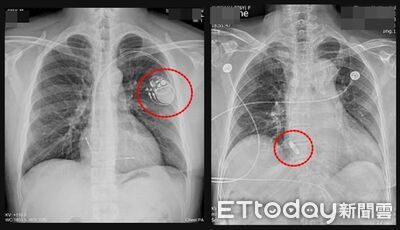

一名76歲女性最近感覺一動就會喘,走2、3階樓梯便須停下來換氣,而且不時會頭暈,就醫檢查後,發現她的心跳最慢時每分鐘僅跳12下,遠低於正常的60至100下,確診「病竇症候群」,經植入右心房無導線心臟節律器後,這才恢復穩定心跳。 《詳全文...》